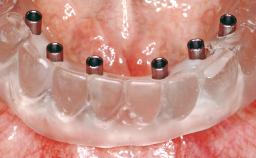

Immediate Loading of Six Implants in the Maxilla and Final Restoration with a Full-Arch CAD/CAM Zirconia FDP

A 63-year-old male patient was referred for a consultation and treatment of partial edentulism in the maxilla. The patient presented with residual anterior teeth and declined a partial removable prosthesis. He reported that the maxillary posterior teeth had been extracted due to mobility and periodontal disease two months before the consultation. The patient’s chief complaint was that his residual maxillary teeth were mobile and that he was unable to chew. The patient’s desire was a stable and comfortable fixed maxillary rehabilitation. The patient was a light smoker (fewer than 10 cigarettes/ day), and his medical history was without significant findings. He was not on any regular medication at the time of consultation. The extraoral examination revealed a normal physiognomy with a correct distribution of the facial thirds. The patient presented a low lip line, and the transition line between teeth and soft tissues was not exposed during a forced smile.

# of Implants 6

Type of Implants One-Piece

Loading Protocol Immediate